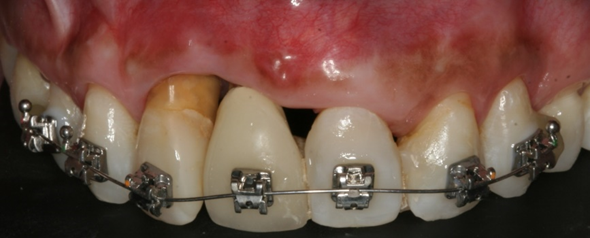

Também foi proposto o tracionamento do elemento 12 com o uso de aparelho ortodôntico para posterior exodontia, a fim de trazer coronalmente todo o conjunto periodontal. O tracionamento ortodôntico— incluindo dente, osso e tecidos moles — é uma técnica eficaz para preservação óssea em dentes com indicação futura de exodontia (Passanezi et al.2019). Assim, o tracionamento coronal é uma alternativa conservadora e previsível para otimizar a futura arquitetura peri-implantar.

Após reavaliação, foi planejada a explantação do elemento 11 e exodontia do 12 e, após seis meses, planejado colocação de implante Cônico HI Implacil Osstem de 3,5x11mm e reabilitação. A paciente não aceitou passar por cirurgia para aumento da espessura e altura de tecido queratinizado, o que poderia melhorar a estética e favorecer a higienização. No entanto, a autonomia do paciente deve ser respeitada e as limitações devem ser explicadas. Nestes casos, o acompanhamento clínico personalizado e manutenções devem ser feitas regularmente para saúde e longevidade do sucesso da terapia de implantes.